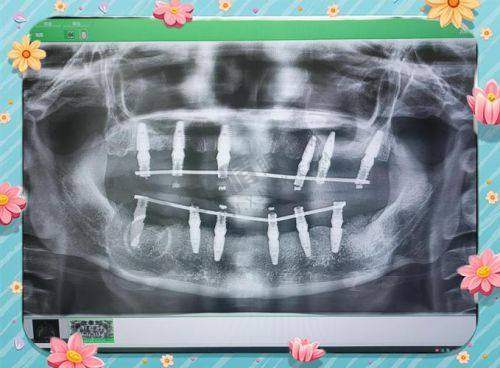

骨干医生团队更是实力雄厚,拥有口腔治疗医生6名,副医生12名,其中包括博士研究生导师4名,硕士研究生导师8名。以刘习强医生为例,他是口腔颌面外科的骨干医生主事,医学博士毕业生,口腔颌面外科博士研究生导师,还是教育部新世纪的非凡人才之一。他主持过多项自然科学基金项目,发表40多篇学术论文,参编6本教材著作,擅长各类口腔治疗、口腔颌面整形、美容种植牙手术、微创拔牙手术、牙齿矫正手术等。

医院的热门医疗项目也备受关注,包括微创种植牙、青少年牙齿矫正、口腔根管治疗、牙周基础治疗、牙齿敏感治疗、复杂的牙髓病治疗、全瓷牙美白、美白贴面手术等,为患者提供了多样化的治疗选择。